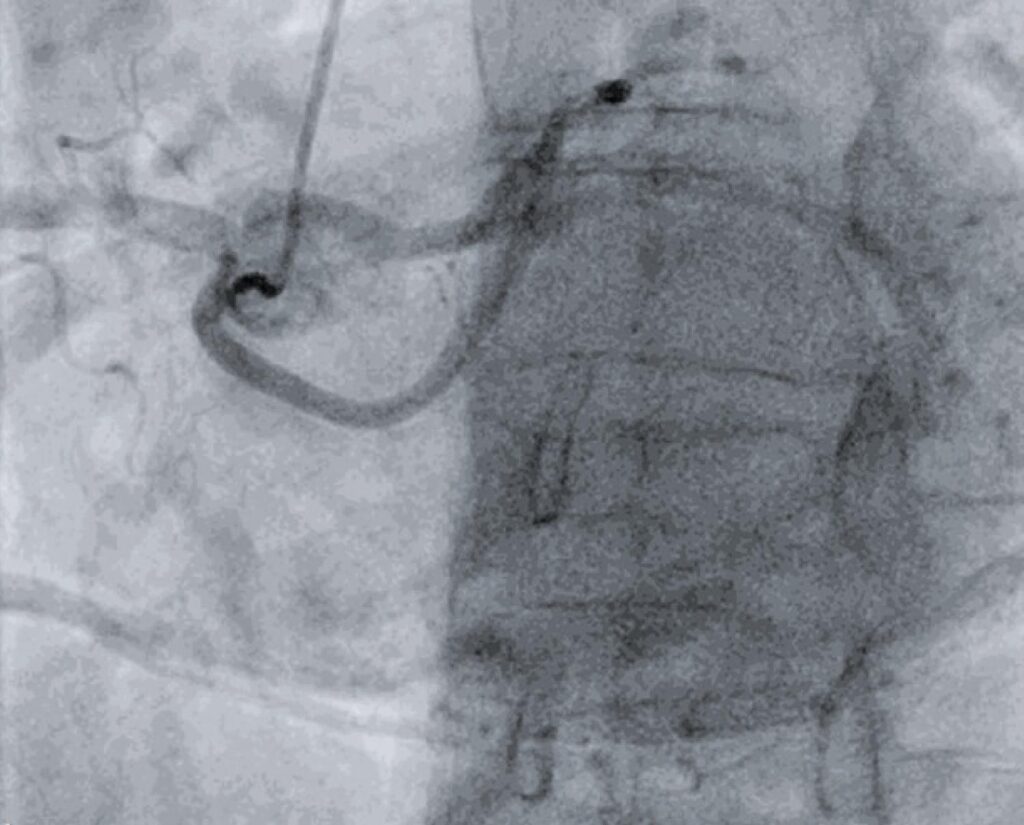

Paciente do sexo feminino, 61 anos, foi encaminhada ao Departamento de Cardiologia por dispneia aos mínimos esforços. Uma ecocardiografia transesofágica revelou válvula aórtica bicúspide com estenose grave e fração de ejeção normal nos dois ventrículos. Realizou coronariografia pré-operatória de rotina. Optou-se por acesso radial direito. Apesar de diversas tentativas, não foi possível visualizar a origem do tronco da coronária esquerda no óstio esquerdo. Realizou-se cateterismo da artéria coronária direita, que mostrou um implante normal no seio direito. Surpreendentemente, os óstios das artérias descendente anterior (ADA) e circunflexa (Cx) foram encontrados no seio direito, estavam separados e com tronco da coronária esquerda ausente. Não foram encontradas outras alterações na angiografia.